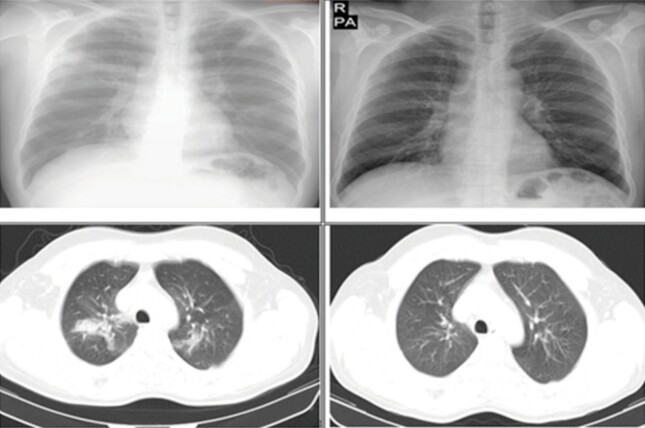

Result: In the final analysis, we included ten patients with a median follow-up of 22 months after initiation of omalizumab. During this follow-up period, the results were associated with a significant reduction in the number of asthma attacks per year, the number of CEP relapses, the rate of hospitalization, the amount of corticosteroids consumed daily, and the total corticosteroid dose. In addition, improvement was observed in the symptom scores and lung functions of the patients. Systemic steroids were completely discontinued in two patients receiving omalizumab treatment. In other patients, the mean steroid dose was reduced by 77.2 percent in the first year of omalizumab treatment and 82 percent in the second year, respectively. Nevertheless, there was no elevation in peripheral eosinophil count, and radiological regression was observed.